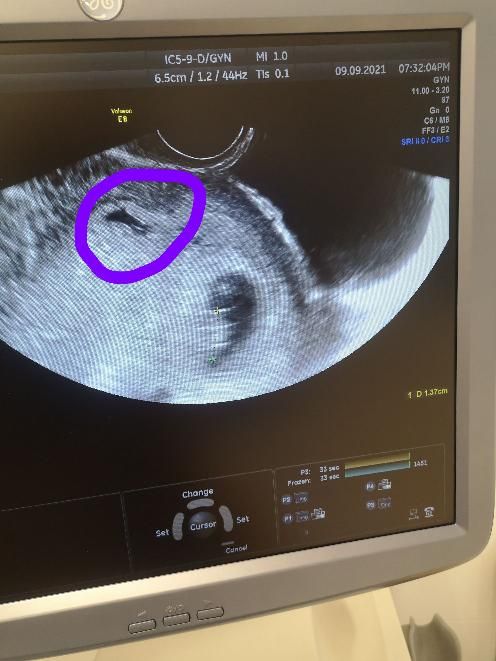

Подскажите пожалуйста, что это рядом с ребеночком?

Всем привет. Живу в Польше, пока переехали в новый город и здесь ещё не нашла толкового врача, на последнем приёме мне не смогла объяснить врач, что это такое, так между делом сказала, что сгусток крови. Так ли это кто знает?

Обычная гематома. Рассосется через несколько недель ) Берегите себя, побольше лежите, ничего не поднимайте тяжелого. Она может выходить в виде коричневой мазни - это норма.